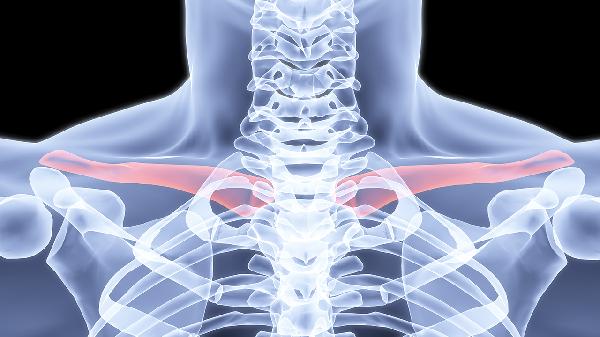

八字绷带或锁骨带的稳定性直接影响愈合质量。固定过松易导致骨折端微动延迟愈合,过紧可能压迫腋神经。每周需调整固定装置,保持骨折端对位良好。